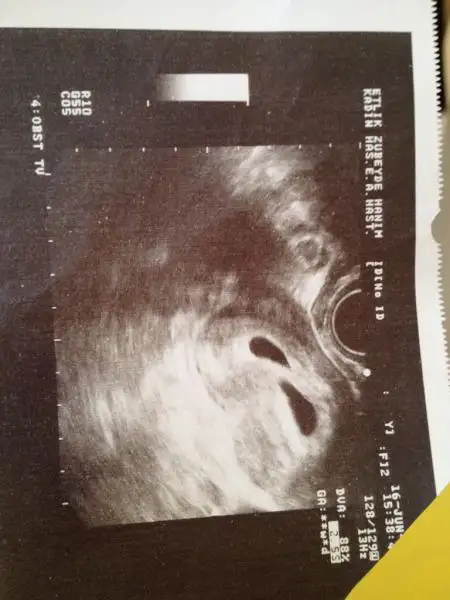

Eki Görüntüle 1176727 Eki Görüntüle 1176728 Eki Görüntüle 1176729 . Dandini bunlar bi öncekiler bgnlü görüntü hastanede kalmş

Kızlat anca yazabilyrm ikizlerim gayet iyilermiş doktor progestan seni mahveder ben sana aynı eş degerde haftada bir iğne vereyim dedi ikizlerin biri 8 haftalık diğeri 7+6 boyları da biri 16.6 mm diğeri 15.5 mm biri sag üst fetüs diğeri sol alt fetüs yazıyo :) bu bebekler bugn yüzümü güldürdüler seviyorum seviyorum kurbaga yavrusuna benzeselerde seviyrm :)